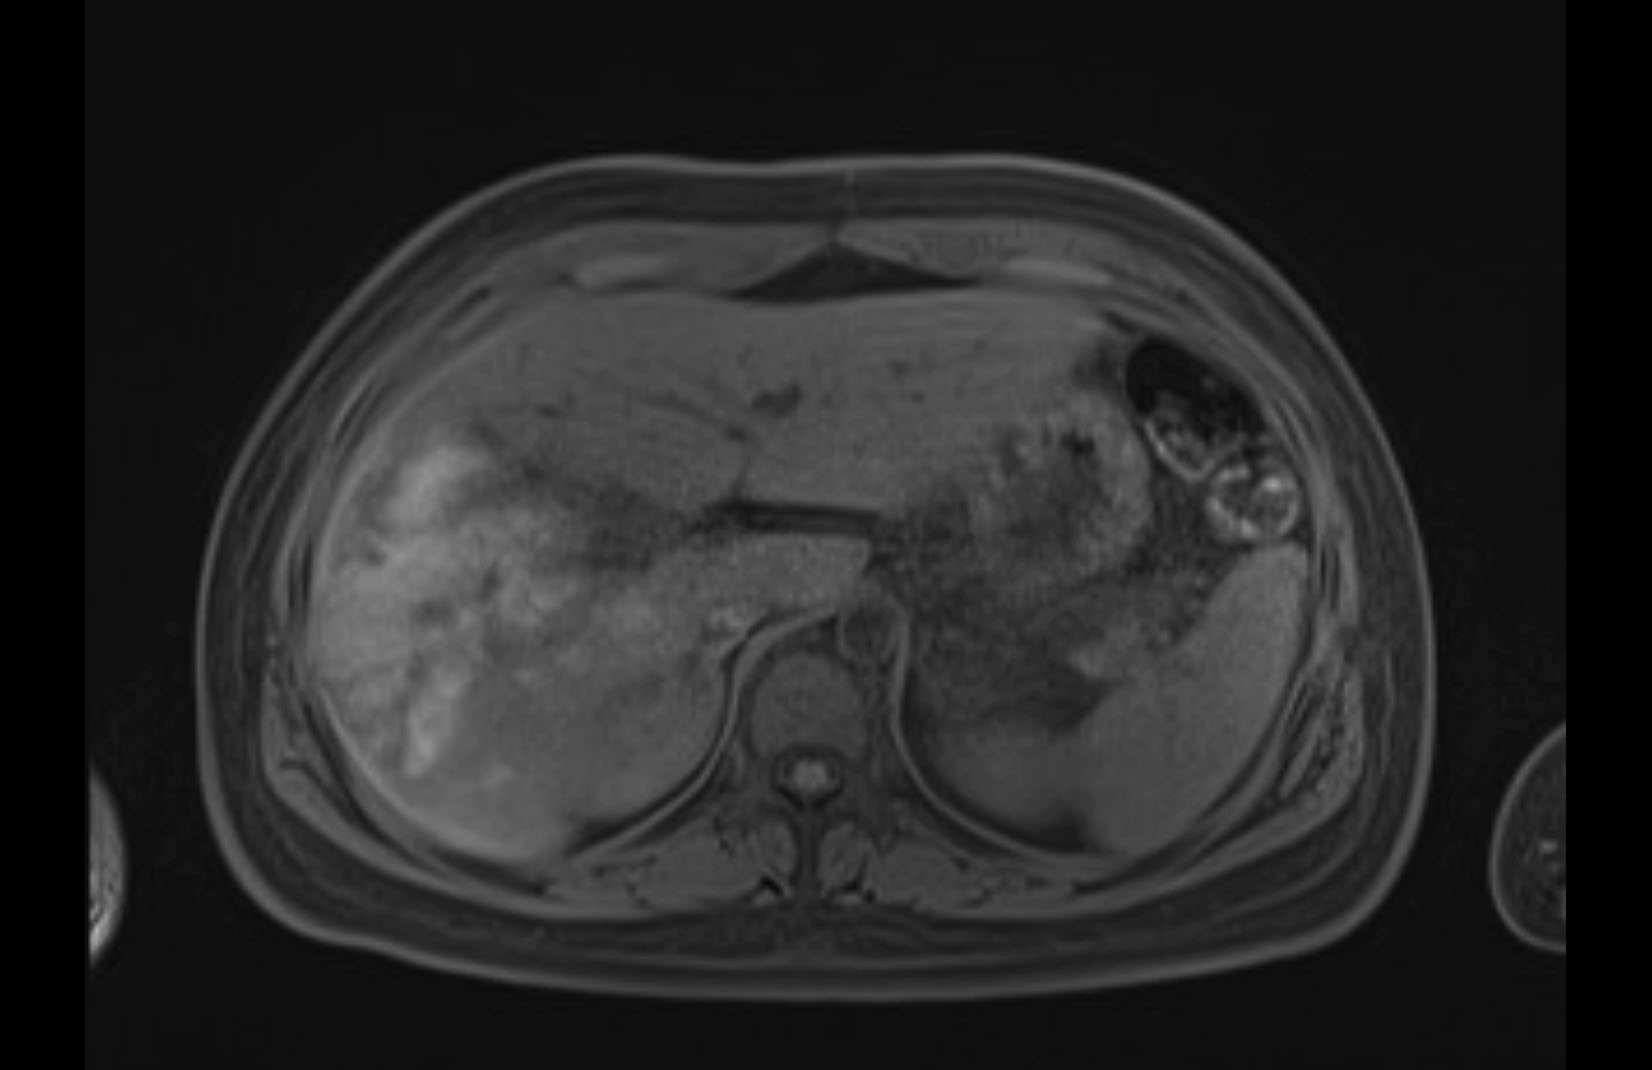

MRI T1

MRI T2

Imaging analysis

Based on initial findings, which issue(s) would you be most concerned about?